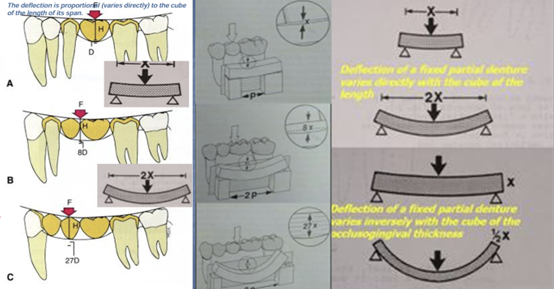

- 橋體越長,形變與彎曲風險會明顯增加;

長牙橋越容易彎、越容易累積應力,這不是單純多一點點而已,而是會被放大。

在固定贋復學裡,這個原理是經典觀念;Shillingburg 的《Fundamentals of Fixed Prosthodontics》明確整理了這個力學原則:橋體撓曲與跨度長度呈立方關係,與咬合齦向厚度呈反比的立方關係。

也就是說,在其他條件近似時,跨度加長,形變會明顯放大,而不是線性增加。這個經典說法在後續贋復文獻中也持續被引用,常追溯到 Stuteville 1934 年的早期報告。